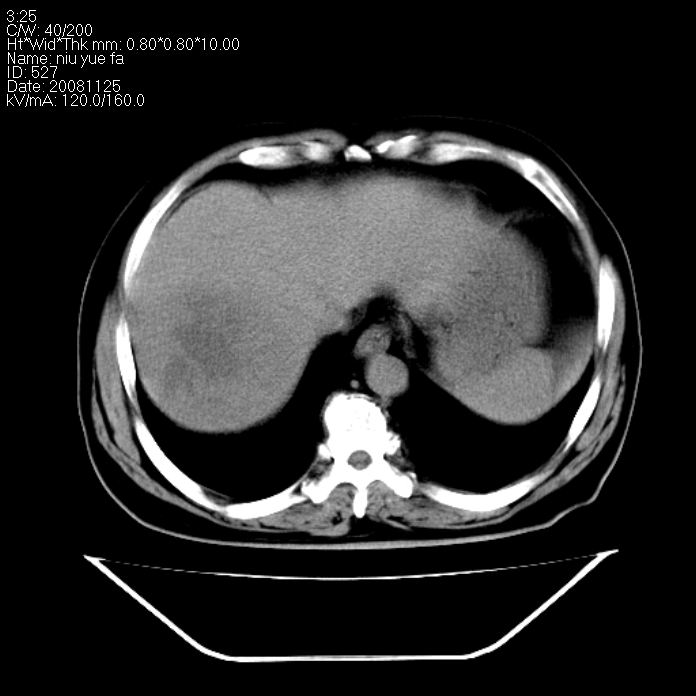

巨块型肝癌,坏死,出血;胆囊结石

1)考虑肝右叶巨块型肝癌并坏死、出血;建议行ct增强扫描检查进一步明确诊断。2)胆囊结石,胆囊炎。

考虑肝右叶巨块型肝癌并坏死、出血;建议行ct增强扫描。胆囊结石。

肝右叶巨块型肝癌并坏死、出血;胆囊结石,胆囊炎。